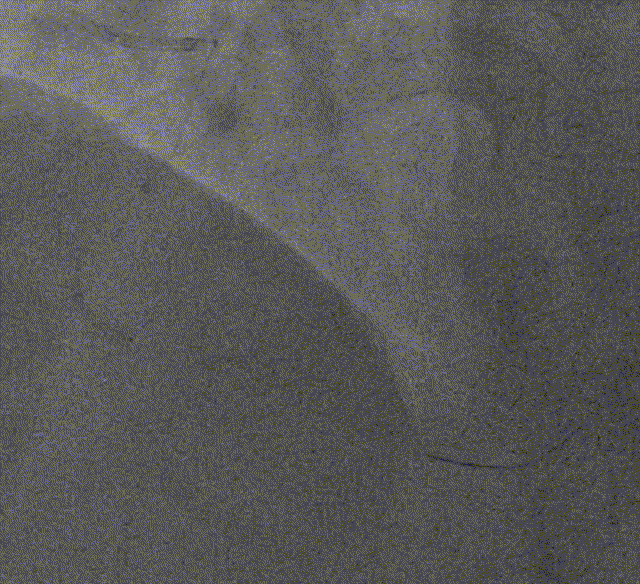

Telescope™导引延长导管前进+Tazuna2.0*15mm球囊*2(期间更换一次)掘进交替进行

更换XT-A为SION blue导丝,Tazuna 2.0*15mm反复扩张